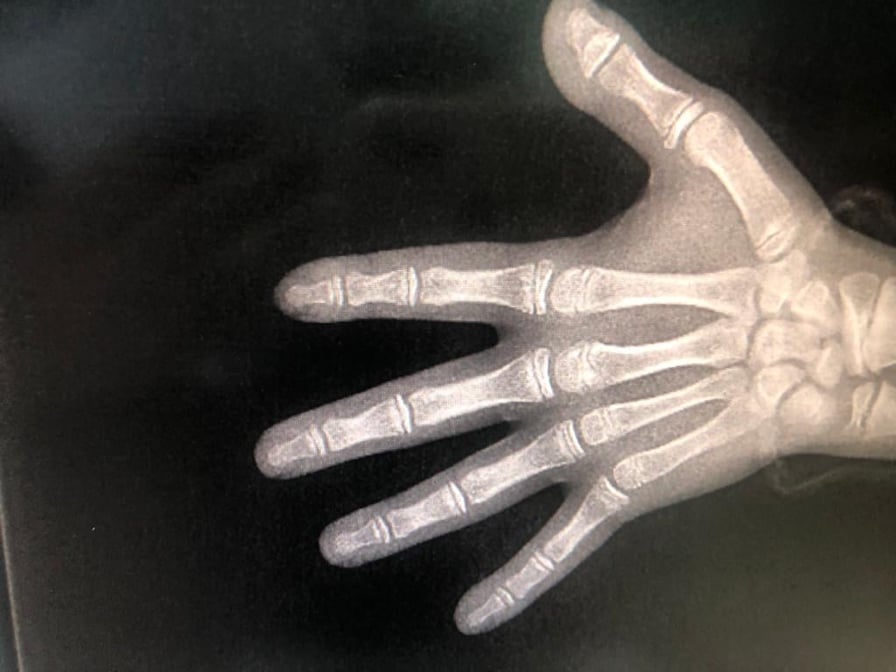

تعتبر معرفة العمر العظمي عند الأطفال أمراً بالغ الأهمية من أجل تحديد ما إذا كان الطفل قد تجاوز مرحلة قفزة النمو أم لا.

ففي حال عدم تجاوزها فإن علاجه سيكون أفضل عن طريق تركيب جهاز تقويم وظيفي يساعد على إصلاح الخلل الهيكلي لديه، أما في حال تجاوزها فسيتمّ اللجوء إلى تركيب جهاز تقويم ثابت.

ويتم معرفة العمر العظمي عن طريق أخذ صورة أشعة سينية واحدة لمعصم اليد وأخرى لأصابع اليد اليسرى.